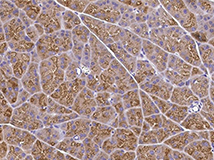

Anti-KLK3/PSA Antibody, Mouse mAb

Applications: IHC-P

(Cat#: 10771-MM02)

Immunochemical staining of human KLK3 in human prostate. Image Credit: Sino Biological US Inc.